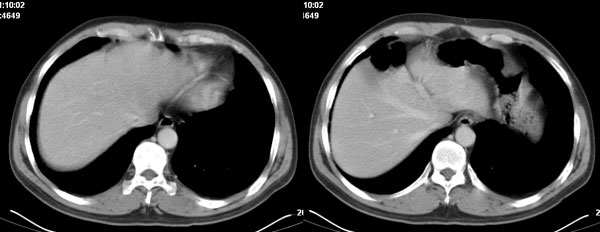

李**,男,46岁,便血1天入院,慢性贫血貌,腹平、软,剑突下压痛,肠鸣音稍活跃,hb大于1g/l,胃镜:慢性浅表性胃炎,b超:1肝内多发性占位 2腹腔内囊性肿块 ,肝内圆形影平扫ct值42.9,动脉期48.6,静脉期58.2,延迟期62.2

影像学表现:1 腹腔前中部、胰腺前方囊实性病灶(个人认为确定有否实性成分存在这是关键,涉及到鉴别诊断,如果是口服阳性造影剂则可明确左侧是不是小肠了),囊性部分囊壁不均,实性部分有强化,与小肠关系较密切,局部小肠受推移;与胰头、胃后壁均有脂肪间隙存在;2 胰腺无异常改变,胰周无渗出;3肝后段包膜下2个小圆形低密度灶,从图像和楼主提供的ct值来看有轻度强化,灶周无片状强化,不似单纯囊肿及肝癌、炎性病变表现;4 腹膜后及腹腔内无淋巴结肿大。

胰腺边界清晰,胰周筋膜不厚,胰周脂肪密度无明显增高;其前方囊实性病灶,边界清晰,增强后实性部分轻度强化;肝内多发边界清晰低密度影,增强后无明显强化(平扫ct值42.9,动脉期48.6,静脉期58.2,延迟期62.2)。